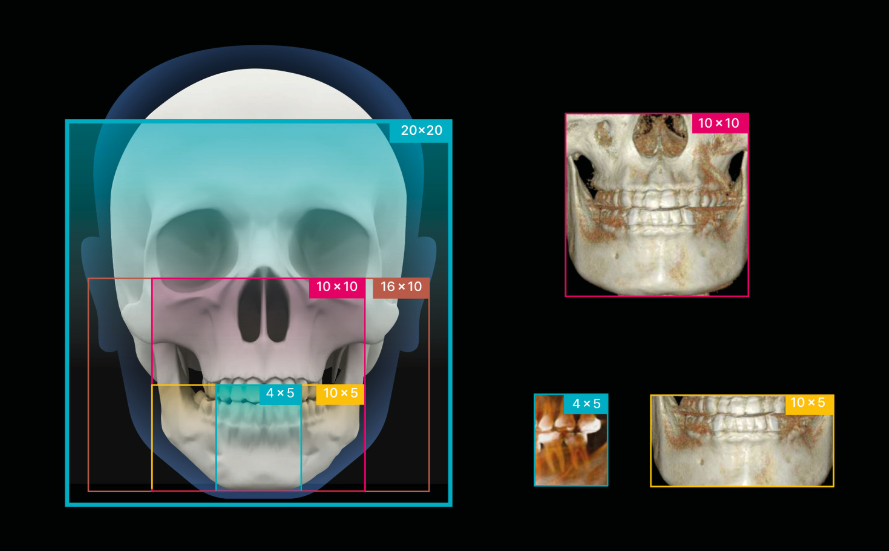

FOV 20 x 20

FOV óptimo para diagnósticos 3D

FOV 20 X 20 máx.

FOV predefinido

Implantología, endodoncia, ortodoncia y ATM simple

Alta Resolución

100μm

FOV 9×5

160μm

FOV 10×10

300μm

FOV 20×20

Imágenes de alta resolución para un diagnóstico preciso

Experimente una claridad de imagen excepcional y volúmenes de escaneo personalizables con RAYSCAN S. Adapte sus exploraciones para satisfacer sus necesidades clínicas específicas, asegurándose de capturar cada detalle intrincado y liberando posibilidades ilimitadas.

Diágnostico de todas las áreas

FOV 4 X 5 cm

70 μm

FOV (cm)

20 x 20

10 x 10

4 x 5

Tamaño de Vóxel (mm)

0.3

0.16

0.07